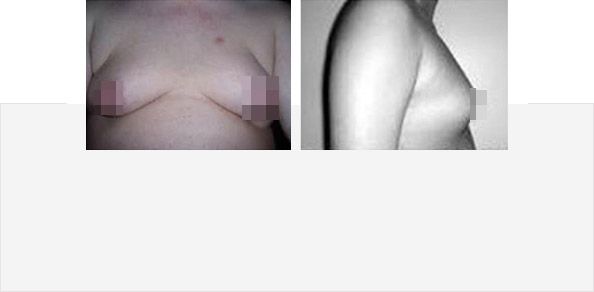

案例一

患 者:张小光(化名) 19岁(男)

主 诉:胸部异常发育,高高突起,看上去有

"C罩杯"大,极度自卑

诊 断:男性乳房发育症

治疗方案:针孔清除术

治疗状况:已摆脱"C罩杯"影响

案例二

患 者:小王(化名) 21岁(男)

主 诉:男生两乳如少女,别人嘲笑自己是女生

诊 断:脂肪和腺体混合型特发性男性乳房发育症

治疗方案:针孔清除术

治疗状况:原本突起的乳房,术后明显恢复

平坦,已回归正常生活